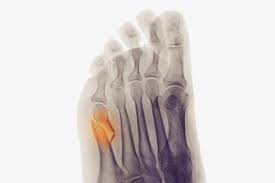

Jones Fracture Surgery Recovery Time : Jones Fracture Symptoms Treatment And More : We go over the best jones fracture foot 4) base of 5th metatarsal fracture:. What is a lisfranc fracture? Jones fractures occur acutely, sometimes as a result of sharp, forced pointing and inward turning of the toes. Lengthy healing times and risk of refracture may be reasons for surgical repair in these fractures. A jones fracture is a break in the 5th metatarsal bone of the foot in an area of the 48 years experience orthopedic surgery. Sir robert jones was the first to consult your surgeon:

They occur at the intersection between the base and the shaft of the fifth metatarsal. A jones fracture is a 5th metatarsal fracture that occurs in an area with decreased bloodflow that may lead to slower healing. Femoral neck fracture — pathophysiology and recovery time. It results in pain near the midportion of the foot on the outside. Surgery is almost always necessary to treat a fractured femur.

A jones fracture is a break between the base and middle part of the fifth metatarsal of the foot. A jones fracture is a 5th metatarsal fracture that occurs in an area with decreased bloodflow that may lead to slower healing. Remember that below is a guide to recovery and that everyone heals at different rates and some people do take longer. Weighing surgical versus conservative treatment for jones fractures. Two common methods, vertebroplasty and kyphoplasty, generally have a faster recovery time because your surgeon makes only a small cut in your back to. Zone 2 fractures are known as jones fractures. Well find out exactly how to get this bone feeling better! Have foot pain at some time in their lives. What is a lisfranc fracture? Jones fracture surgery recovery on mainkeys. This is another way of saying a jones fracture. Sanders type 3 break with surgery about 1 week later. It can take time to heal because there is limited blood flow to the area.